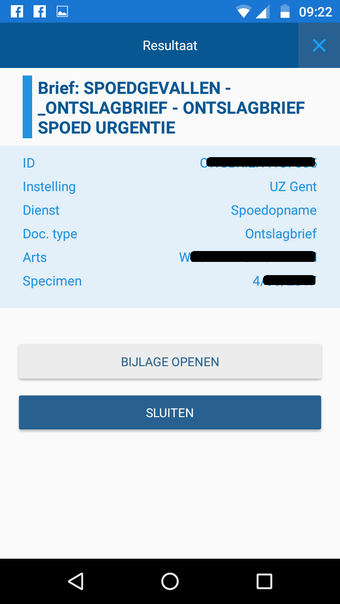

CoZo est une application de santé électronique qui permet aux patients et aux médecins de communiquer entre eux et de partager des informations médicales. Elle a été développée pour répondre aux problèmes du système de santé actuel, caractérisé par un manque de communication entre les patients, les médecins et les autres professionnels de la santé.

CoZo permet aux patients de prendre une part active dans leur propre santé et d'être traités comme des participants actifs dans le processus de soins. Les patients peuvent utiliser l'application pour enregistrer leurs données de santé, qu'ils peuvent ensuite partager avec leurs médecins. Les médecins peuvent utiliser l'application pour enregistrer l'historique médical de leurs patients, poser un diagnostic et suggérer un plan de traitement.